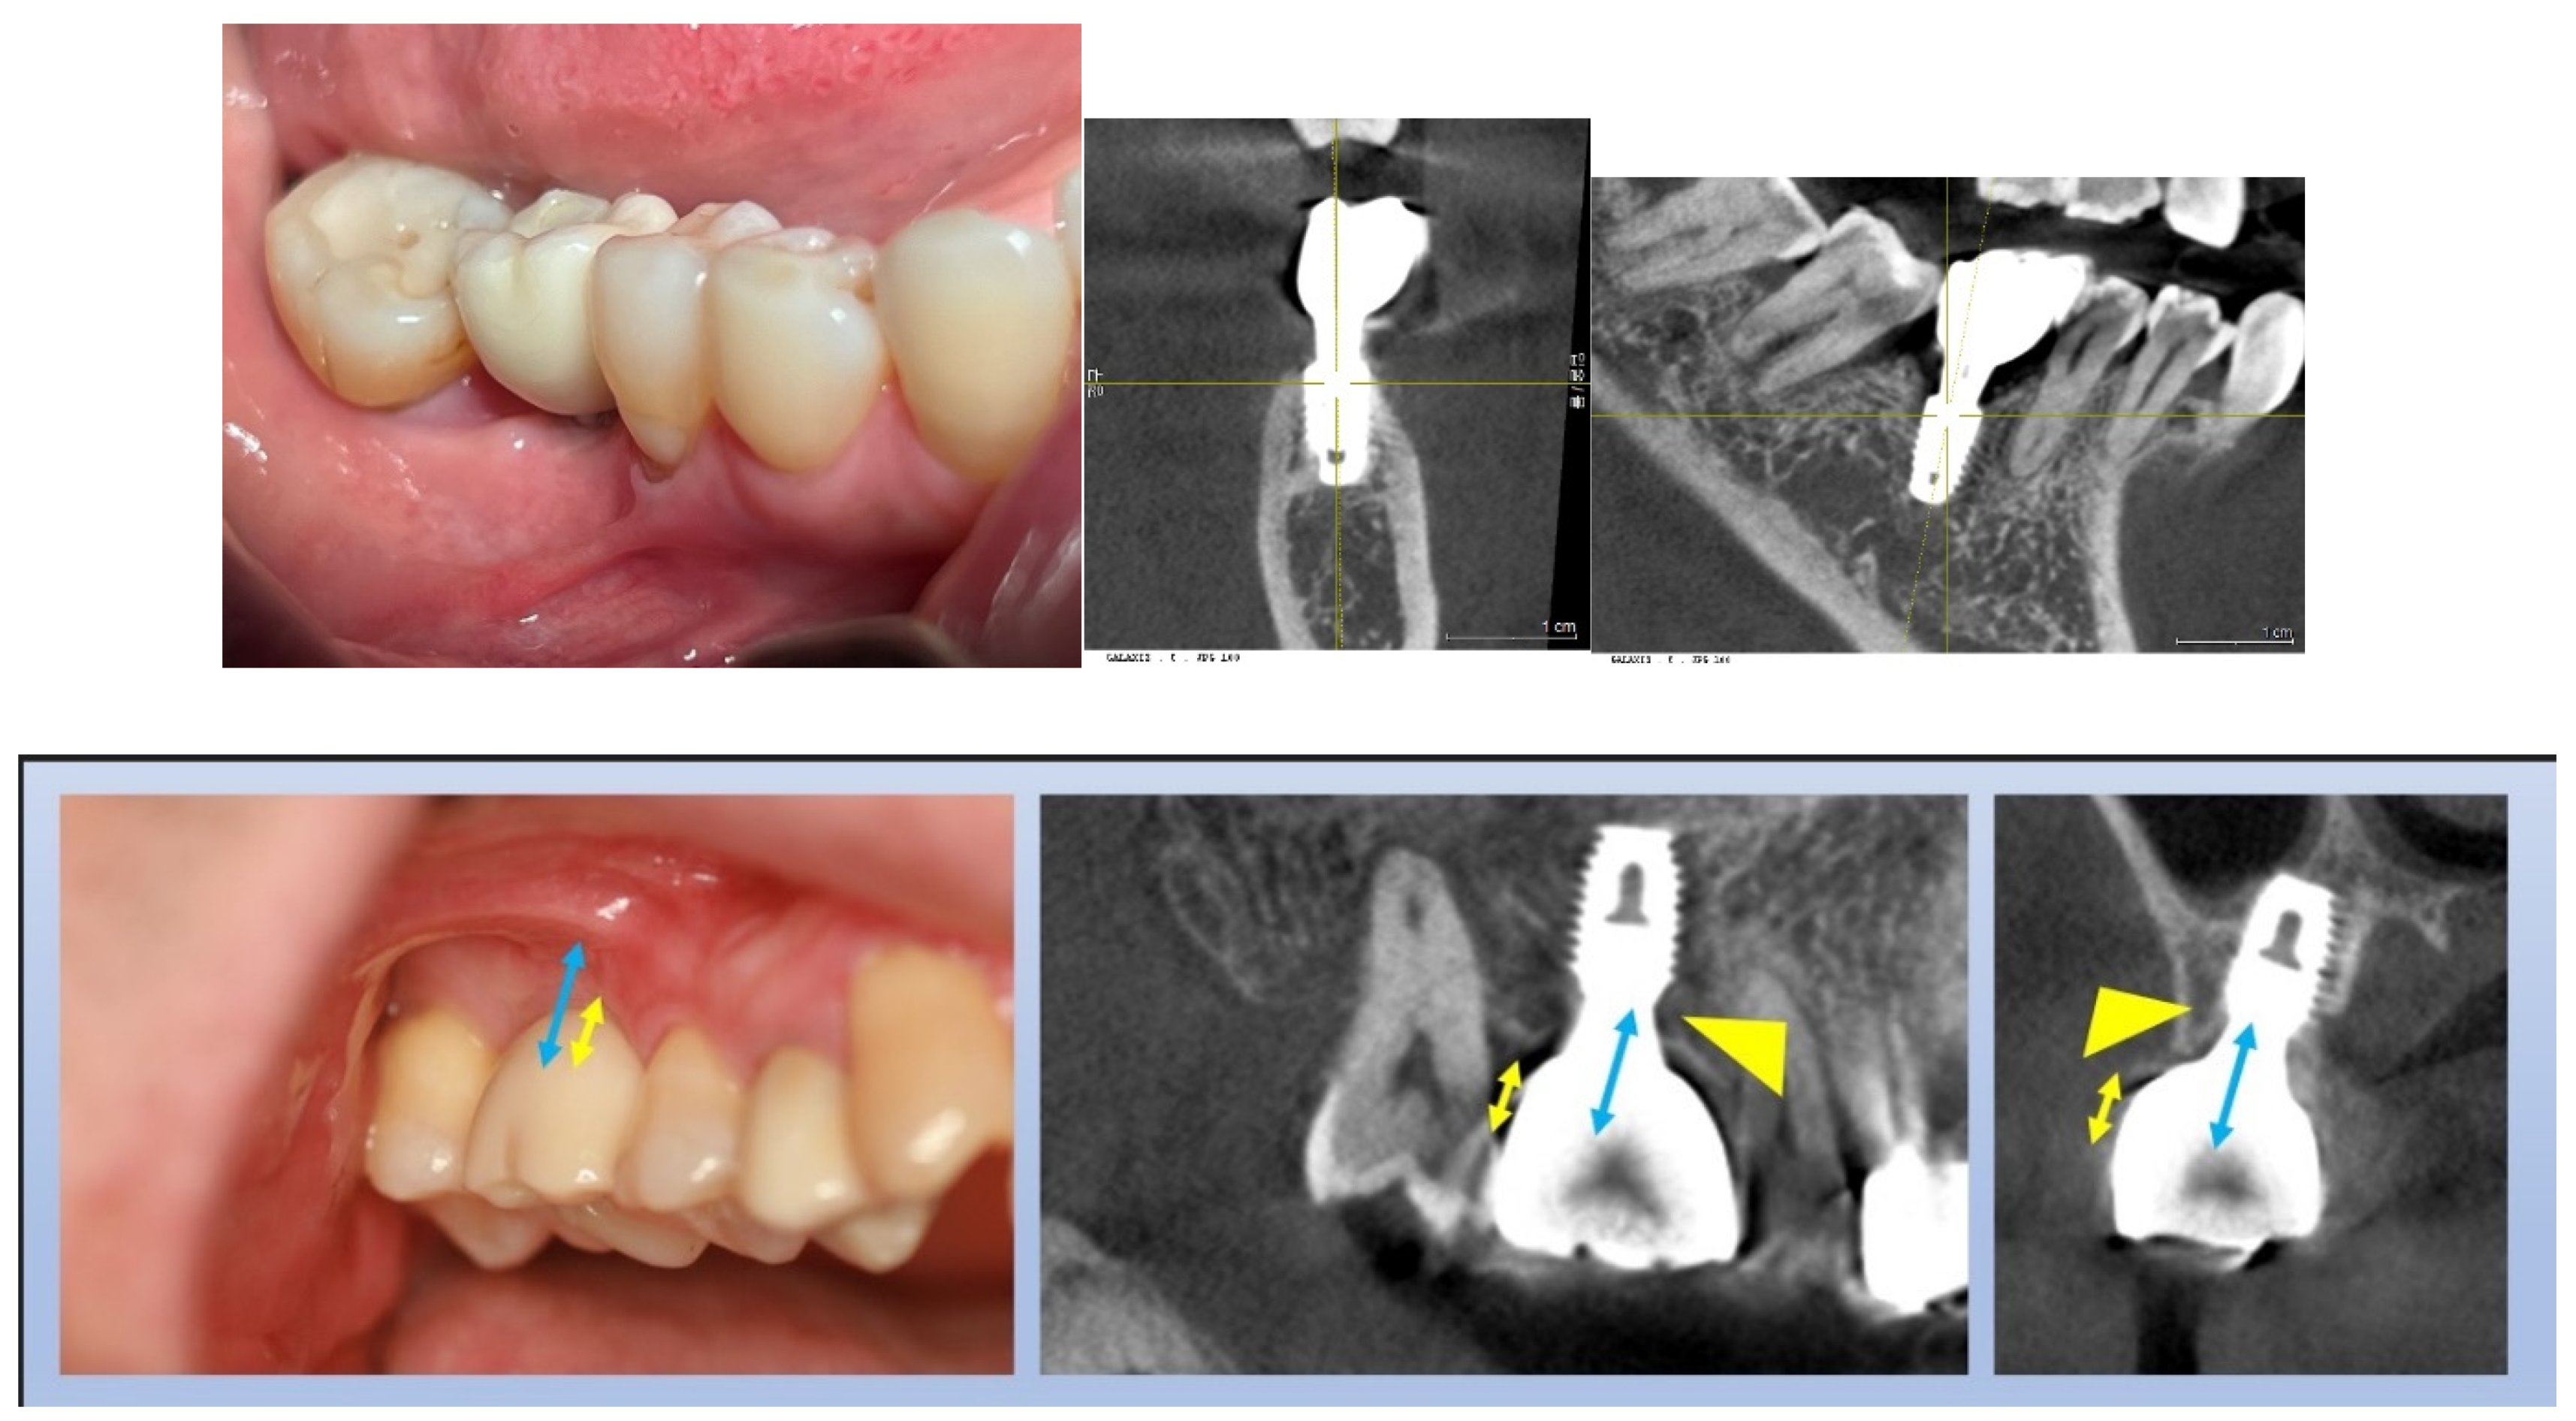

Figure 21. Visualizing Submucosal Areas during Abutment Repair. This figure shows the submucosal area exposed during the repair of a broken abutment neck after extensive use. It clearly depicts the Transitional Zone (TZ) and marginal zone, which extend obliquely or even horizontally along the mesiodistal sides. Notably, the subcrestal zone is absent on the buccolingual sides, indicating that the implant was initially placed at the epi-crestal level. This image provides a detailed view of the soft tissue layers affected by the placement level of the implant.

Figure 23. Illustrating the Scalloping Effect. This figure demonstrates the scalloping effect, emphasizing the importance of using the midfacial point, rather than the interproximal point, as the reference for implant placement. It shows that to accurately create a prosthesis with a natural emergence profile, the scalloping effect distance (approximately 2 mm) must be added to the vertical distance from the fixture-abutment joint to the crestal bone level as seen in plain X-rays. This adjustment ensures that the final prosthesis aligns correctly with the natural contour of the gingiva, enhancing both aesthetic and functional outcomes.